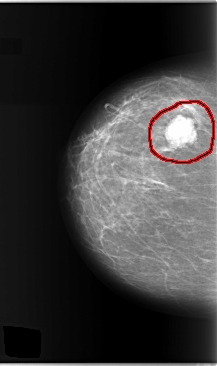

FILE: C_0147_1.RIGHT_CC.OVERLAY

TOTAL_ABNORMALITIES 1

ABNORMALITY 1

LESION_TYPE MASS SHAPE LOBULATED MARGINS MICROLOBULATED

ASSESSMENT 5

SUBTLETY 5

PATHOLOGY MALIGNANT

TOTAL_OUTLINES 1

BOUNDARY